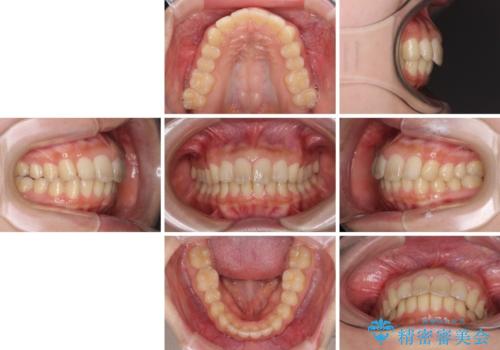

就職前にきれいな歯並びにしたい 大学生のインビザライン矯正

改善の期待できない口元の突出感改善を希望されたため、いたずらに治療期間が延びましたが、きっちりと仕上がりました。